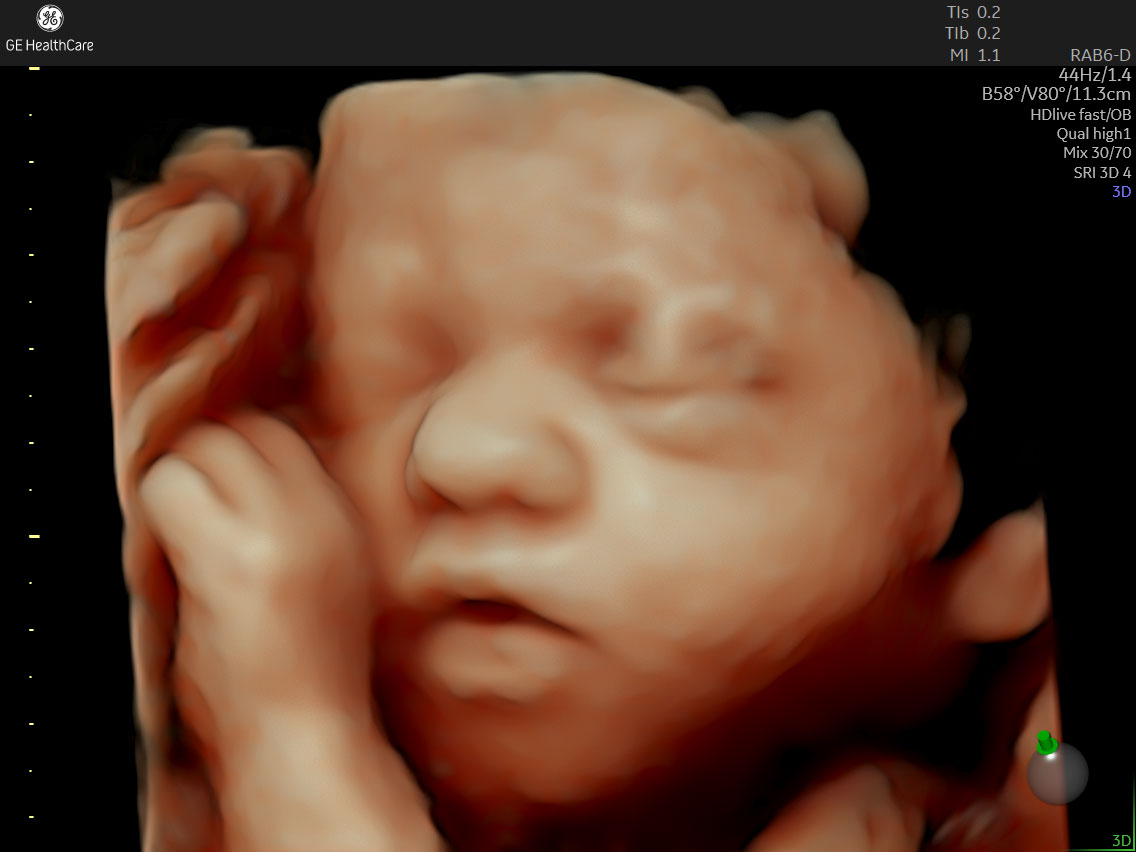

超音波検査装置

GE volson Signature 18

鮮明な4Dエコー画像をご覧いただける超音波検査装置です。

撮影した画像はQRコードで保存ができますので、おなかにいる赤ちゃんの画像をお持ち帰りいただけます。